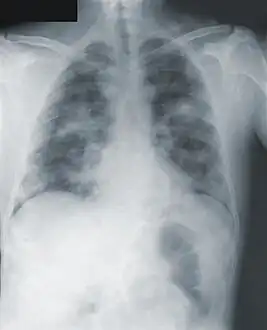

Image -primary pneumonic plague obtained on illness days 2, 3, and 18 shows bilateral lower lung zone predominant airspace disease associated with bilateral pleural effusions -

Chest x-ray of pneumonic plague showing bilateral, diffuse interstitial pleural infiltrates, and accompanying consolidation. As well as, what appeared to be marked, mediastinal adenopathy.